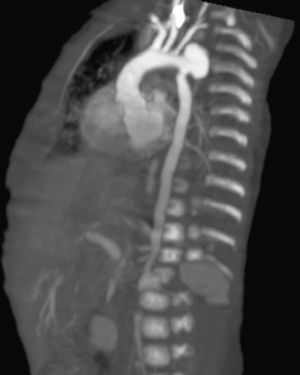

While performing the first echodopplercardiogram, a dilated descending aorta was observed, corroborated by a postsurgical repair of the PDA echocardiography, with an aneurysm of the aortic arch distal to the subclavian artery and the presence of thrombus 4cm×3cm at the mouth of superior vena cava; an angiotomography demonstrated an aortic aneurism, a probable aortic coarctation, plus an abdominal aortic aneurysm (Fig. 1). At diagnosis, the patient had a normal platelet and white blood cell count, anemia, hypocomplementemia at the expense of C3, increased factor VIII and positive PCR.

When control echocardiograms were performed for the underlying cardiac disease, aortic dilatation was noted, being more evident in the 3rd week of life; because of this finding, we opted to confirm it through a CT angiography (Fig. 2)